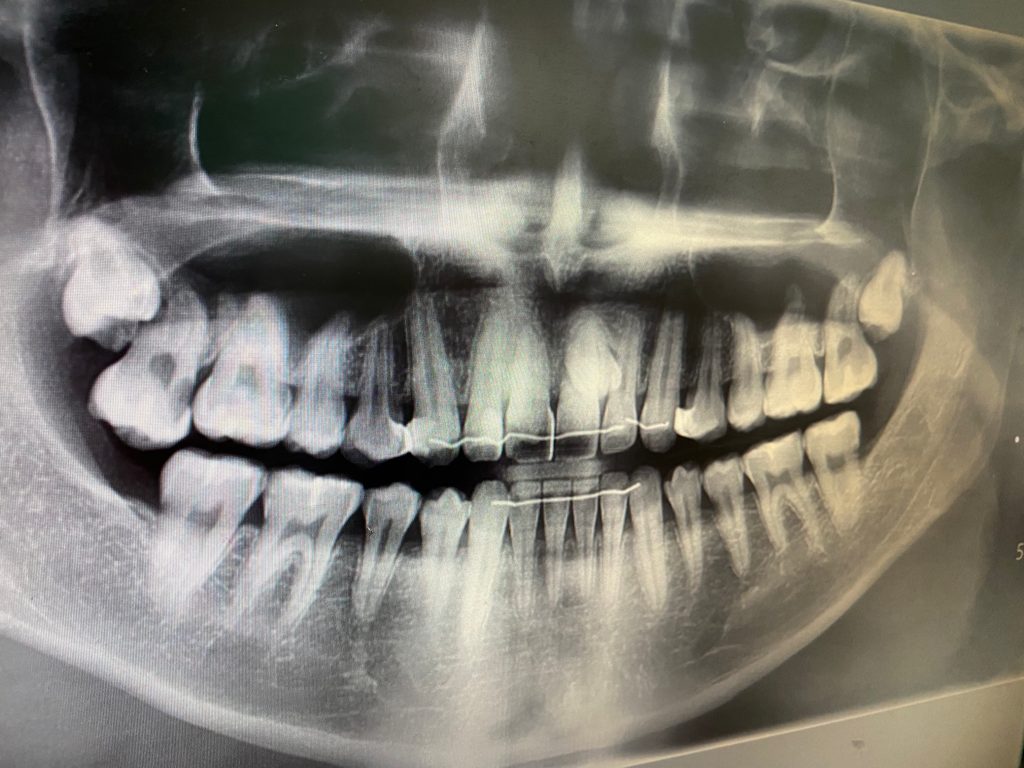

<아래 사진 기준 왼쪽 위 어금니에 신경치료를 받습니다.>

• 1번 째 사진

오른쪽위 어금니가 많이 썩어 보이네요. 일단은 아프면 진통제 말고는 따로 먹을수 잇는 약이 없습니다. 약국에서 진통제를 드시면서 빨리 가셔서 신경치료를 받으시는게 좋습니다.

충치가 매우 심하여 신경치료가 필요해보입니다.